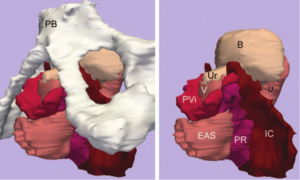

Virtual Cystoscopy - A Surgical Planning and Guidance Tool

Publication: Arch Ital Urol Androl. 2006 Mar; 78(1):23-24.

Authors: Braticevici B, Onu M, Bengus F.

Institution: Clinical Hospital, Bucharest, Romania.

Background/Purpose: Image guided-surgery systems facilitates surgical planning phases of endoscopic procedures. In this paper, we used a software package for 3D surface model generation and vizualization of the urinary bladder, based on magnetic resonance (MR) cross sectional images of the pelvis. The patients group consisted in 6 patients diagnosed with urinary bladder tumour. They were submitted to MRI exam. Twelve consecutive cross sectional images of the pelvis were aquired (TR (repetition time) = 600 msec, TE (echo time) = 19 msec, slice thickness = 6 divided by 7 mm, FOV (field of view) = 36 cm. All these images were transferred to a personal computer running the 3D Slicer software. We obtained, for each patient, a 3D model of the pelvis including the urinary bladder. In This way, the surgical enviroment was simulated and we are able to investigate the bladder by virtual cystoscopy. The virtual endoscopy may be used as a tool in the preoperative training and in surgical planning.